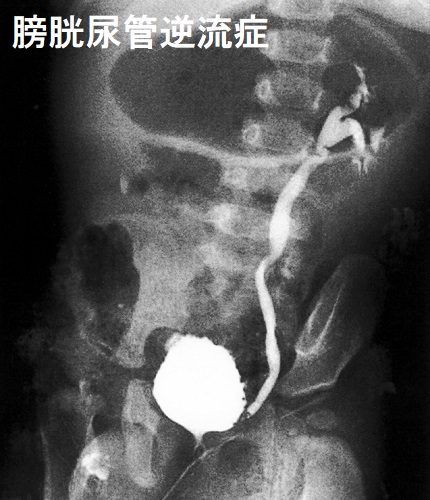

急性腎盂腎炎などの尿路感染症を繰り返す小児は、膀胱尿管逆流(VUR:Vesicoureteral reflux)の可能性があります。

腎臓と膀胱をつなぐ尿管は、腎臓で作られた尿が膀胱へ流れるパイプです。正常では、膀胱から尿管へ尿が逆流しないような構造になっていますが、この逆流防止機能が弱いと膀胱尿管逆流(VUR)が起きます(尿管膀胱移行部で、膀胱壁内尿管のトンネル構造発達が不完全)。

膀胱尿管逆流(VUR)が起きると、膀胱内の細菌が腎臓に送られ、急性腎盂腎炎などの尿路感染症を繰り返します。その結果、腎実質の瘢痕化により、高血圧、慢性腎不全に至ります。

膀胱尿管逆流(VUR)に伴う逆流性腎盂腎炎に甲状腺機能低下症を合併していて、実は甲状腺が原因の慢性腎不全だった報告があります(Arch Dis Child. 2000 Sep;83(3):251-2.)

膀胱尿管逆流(VUR)による逆流性腎盂腎炎で、慢性破壊的な間質性腎炎から甲状腺様病変が生じる場合があります(Pathol Res Pract. 1983 Mar;176(2-4):284-96.)。